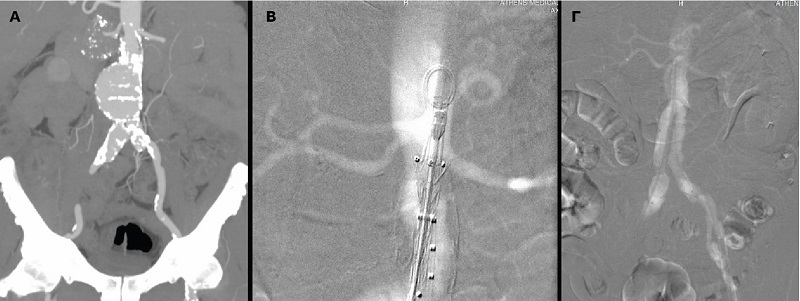

Με επιτυχία πραγματοποιήθηκε, για πρώτη φορά στην Ελλάδα, στο Ιατρικό Κέντρο Αθηνών, η διαδερμική ενδαγγειακή αποκατάσταση κοιλιακού ανευρύσματος μόνο με τη χρήση διοξειδίου του άνθρακα (CO2) και χωρίς καθόλου ιωδιούχο σκιαγραφικό. Η νέα, καινοτόμος τεχνική εφαρμόστηκε από την αγγειοχειρουργική ομάδα του κ. Θεοδόσιου Μπίσδα, MD, PhD, Αναπληρωτή Καθηγητή Αγγειοχειρουργικής στην Πανεπιστημιακή Κλινική Muenster Γερμανίας, Ενδοαγγειακό Χειρουργό, Φλεβολόγο, Κλινική Αγγειακής και Ενδοαγγειακής Χειρουργικής.

Αξίζει να σημειωθεί ότι η ποιότητα της αγγειογραφίας ήταν ισάξια με αυτήν του ιωδιούχου σκιαγραφικού, τα μοσχεύματα τοποθετήθηκαν με απόλυτη επιτυχία αποκλείοντας το ανεύρυσμα και η νεφρική λειτουργία του νεφροπαθούς ασθενούς δεν επηρεάστηκε καθόλου.